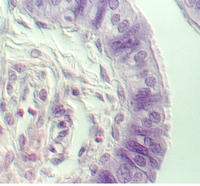

Simple Columnar Epithelium